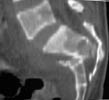

A 28 year old male jumped from the 4th floor on 11-25-2000 sustaining an L1 burst fracture that has been fixed anteriorly by the neurosurgeon with a strut between T12 and L2. A Kaneda device was placed anteriorly as well. My concern is the pelvic ring injury. There are bilateral sacral fractures through the foramen and a transverse element through the sacrum between S2 and S3. the lower part of the sacrum is displaced forward. Anteriorly there are right superior and inferior pubic rami fractures.

MR1

MR2